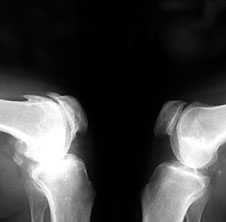

3. Заострение краев суставных поверхностей мыщелков бедренной и большеберцовой кости, чаще в медиальном отделе сустава (связано с большей нагрузкой на этот отдел сустава), особенно при наличии варусной деформации сустава; реже - в латеральной части или одновременно в обеих половинах суставной поверхности (рис. 2).

Рис. 2. Rо-графия коленных суставов в боковой проекции.

Артроз феморопателлярных суставов (больше слева). Артроз коленных суставов (I ст по Kollgren справа, IV ст. по Kollgren слева)

При прогрессировании артроза коленных суставов (соответствует 3-4 стадиям артроза по Kellgren):

• нарастает сужение суставной щели

• развивается субхондральный остеосклероз в наиболее нагруженной части сустава

• появляются множественные крупные остеофиты на боковых, передних и задних краях суставных поверхностей

• редко обнаруживаются субхондральные кисты

Вторичный синовит с развитием субпателлярной или подколенной кисты Бейкера:

• суставные поверхности бедренной и большеберцовой кости уплощаются, становятся неровными и теряют свою анатомо-функциональную дифференциацию

• многогранную неправильную форму преобретает сесамовидная кость (fabella)

• могут обнаруживаться обызвествленные хондромы

• редко возможно развитие асептических некрозов мыщелков костей.